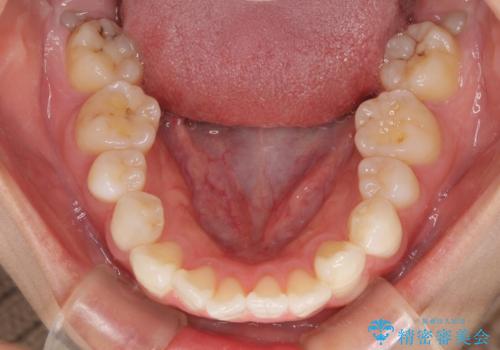

- 八重歯と口元の突出感を気にして来院された患者様です。

歯列が前方に突出しており、上下の正中がズレていたため、左側は上下第一小臼歯を、右側は上下第二小臼歯を抜去し、ワイヤー装置による矯正治療を行うこととしました。